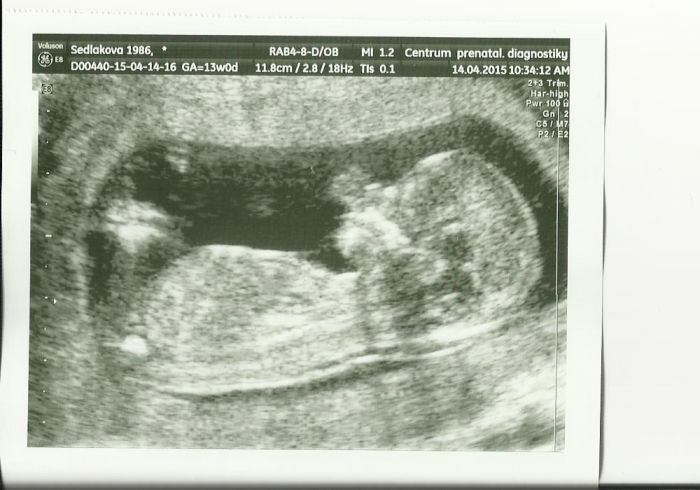

Miru nám to právě vždy vyšlo napoprvé jen to nedopadlo.Byla to pokaždé náhoda a nakonec to vyšlo.Je pravda že jsem vždycky říkala,že už se na to vyprdnu,ale jak proběhla první ms tak touha mít ještě jedno byla vždy větší. Podle doktorky to zatím vypadá na holčičku,tak je možný, že předtím to byly všechno kluci. Ale jsem ráda, že malý je zdravý a to je nejdůležitější :-) Přikládám fotku z posledního utz